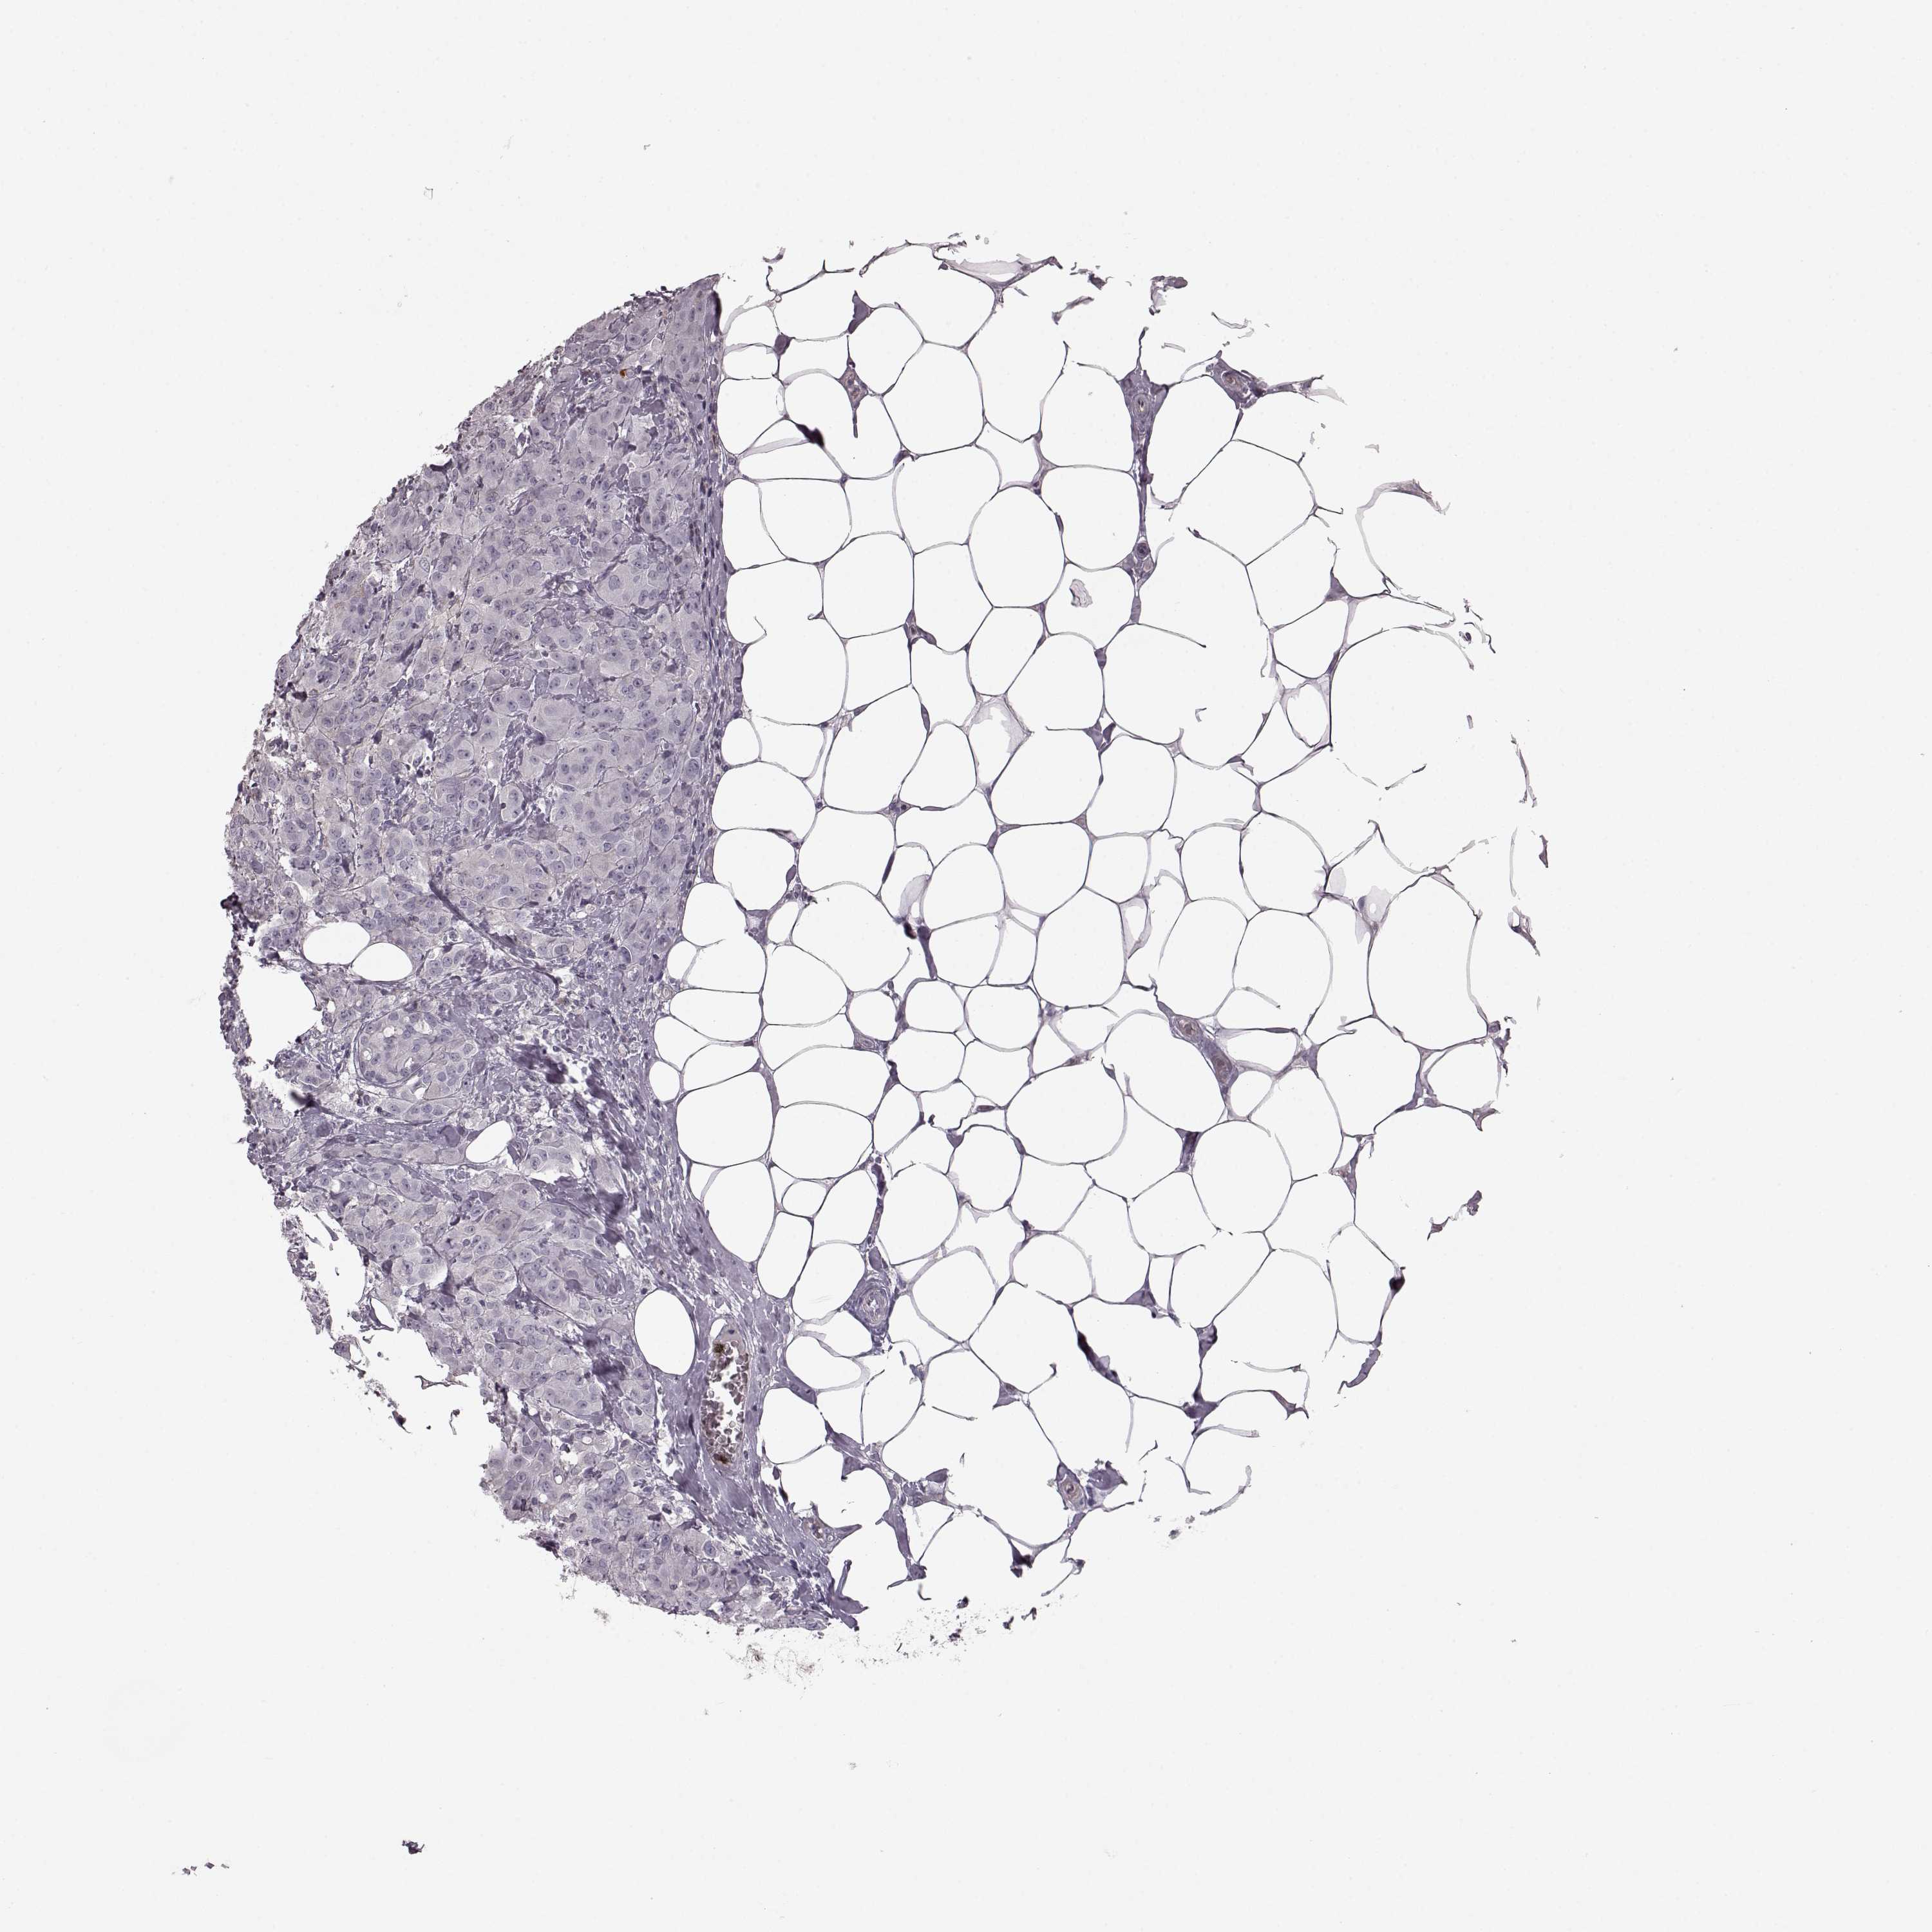

CANCER BREAST CANCER Show tissue menu

BRCA TCGA BRCA VALIDATION PROTEIN EXPRESSION